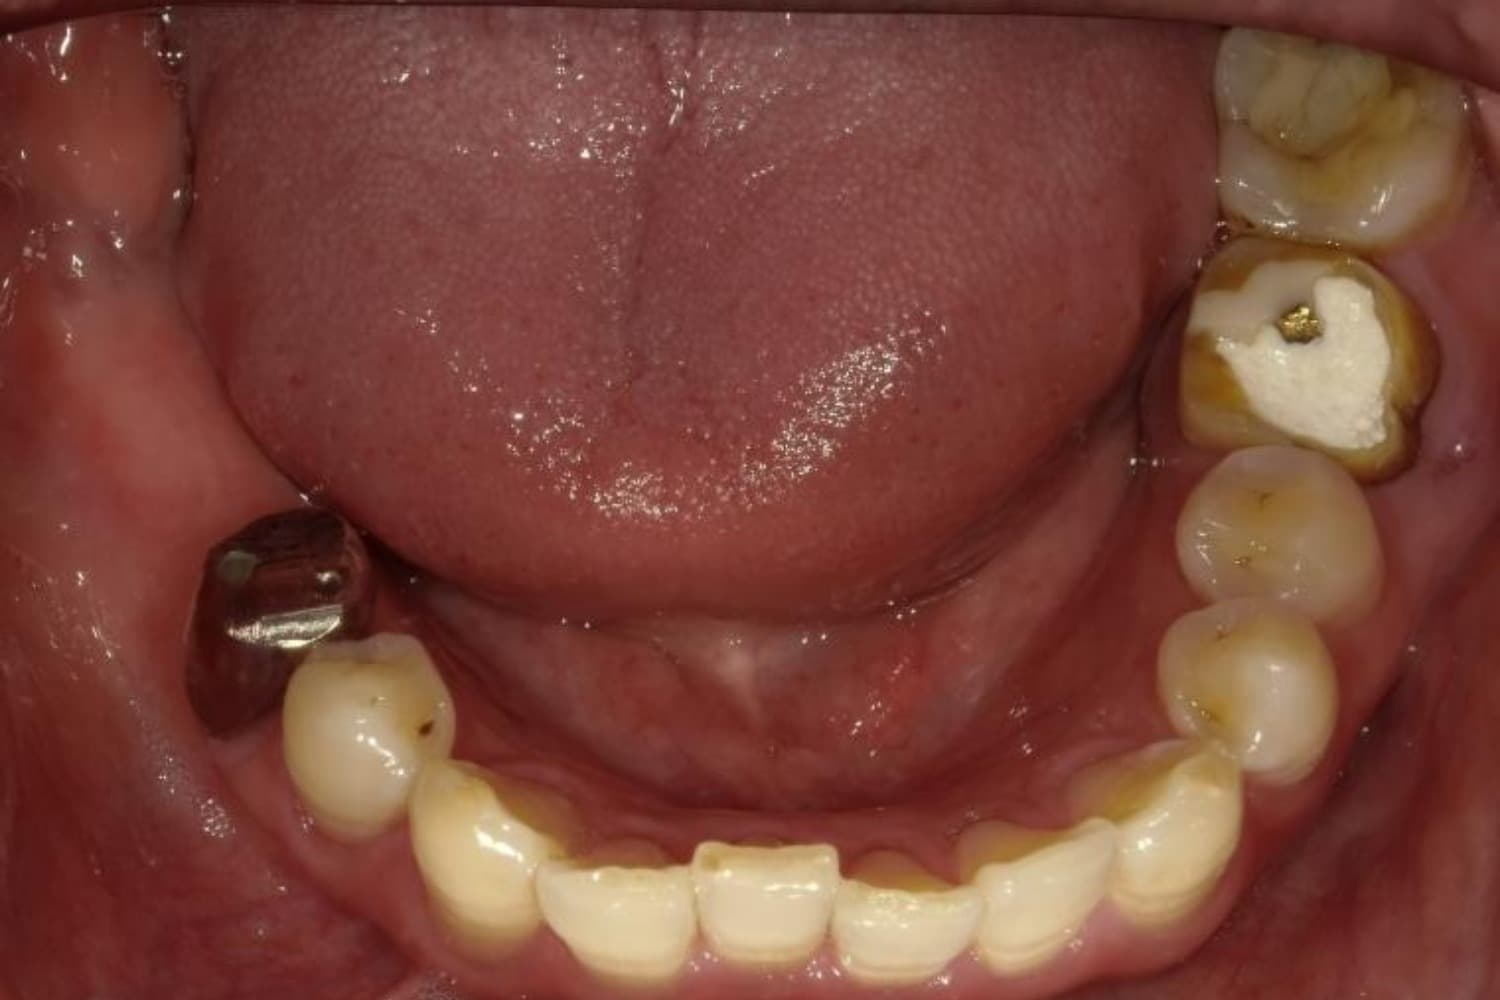

下顎大臼歯3本欠損症例

Before

After

左下第一大臼歯は保存が困難な状態であったため抜歯をおこないました。あわせて、ご来院時から欠損していた右下第一・第二大臼歯も含め、欠損部の補綴方法についてご説明し、インプラント治療を選択されました。

主訴

左下の第一大臼歯は別の医院で治療中でしたが、治療が思うように進まず、加えて他の箇所にも痛みが続いたことから、当院にご相談いただきました。

治療期間

10ヵ月

費用

140万円

副作用・リスク

インプラント治療は外科的な処置を伴い、多少の腫れや痛みが出ることがあります。 多くの場合は鎮痛薬で和らげることができます。